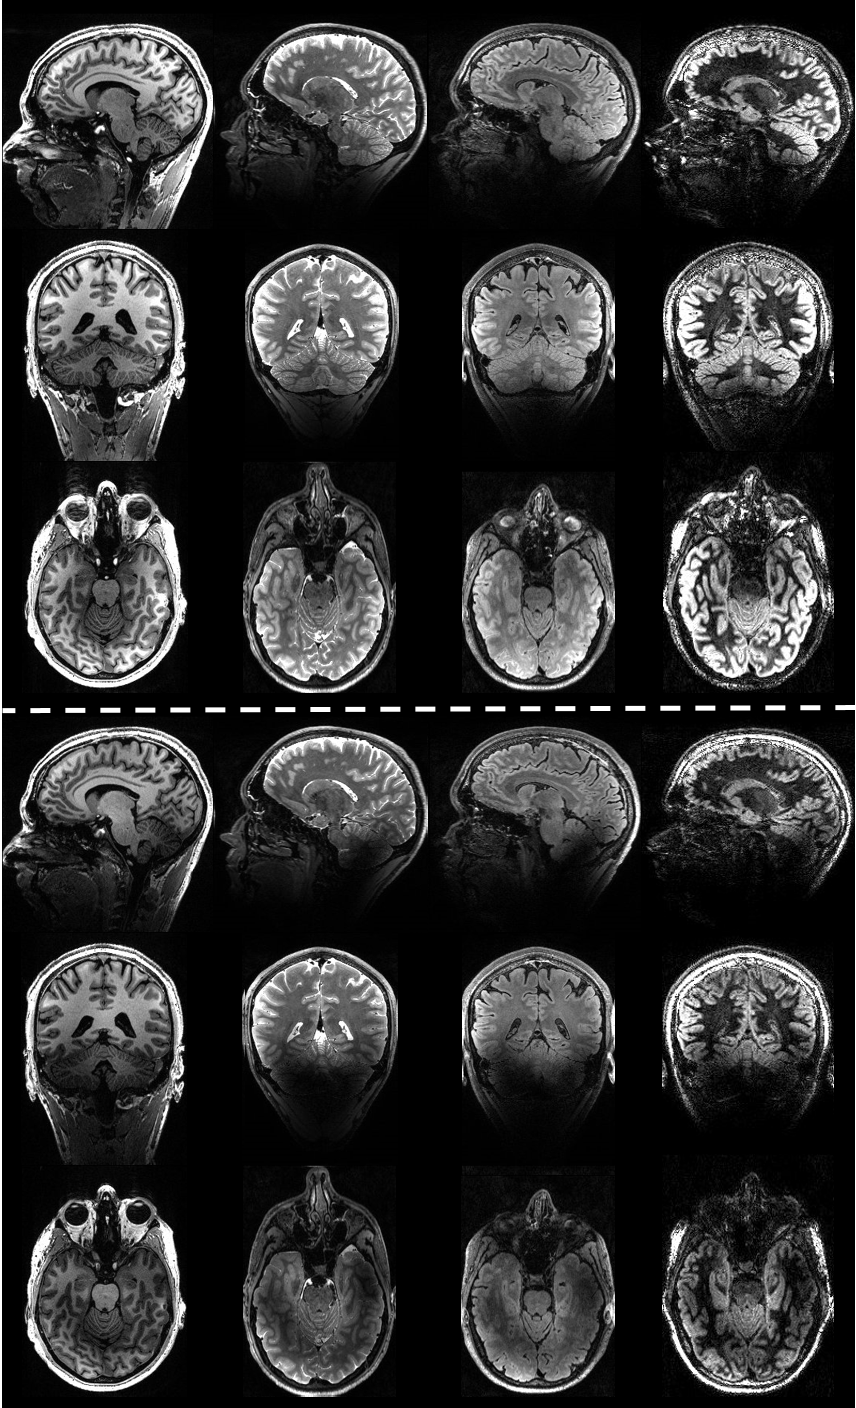

In vivo imaging of the human brain with the Iseult 11.7-T MRI scanner

Nature Methods. 2024. doi: 10.1038/s41592-024-02472-7.

First in vivo images of the human brain revealed with the Iseult 11.7T MRI scanner

Opening New Horizons With The First Human Brain In Vivo Experiments At 11.7T

Proceedings of the ISMRM 2024, Singapore, p0523.